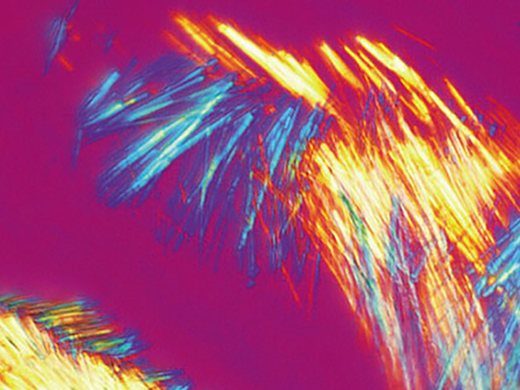

偏光观察

将检偏镜插入物镜转盘,即可利用BX46显微镜进行偏光观察。可以用旋转载物台取代标准机械载物台,进一步改善观察流程。

多用途BX46系统不只是台显微镜,它可以轻松组装成一个复杂的成像系统,满足任何应用需求。从研究工作的机型到用于会议的单机显微镜。我们的数码相机和成像软件可以在所有临床诊断时以高像素色彩保真度采集染色的组织切片。